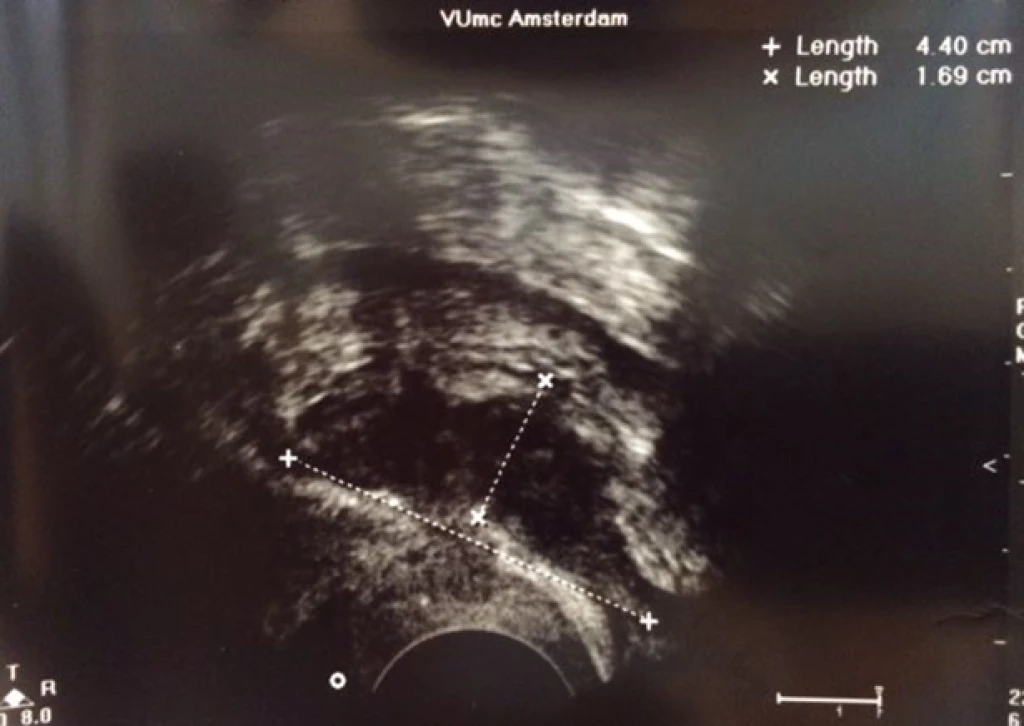

Diepe endometriose met darmbetrokkenheid

Diepe endometriose met darmbetrokkenheid bij dezelfde patiente gezien door MRI, TVE en na operatie: diepe endometriose (zie rode pijl) met musculaire infiltratie in de anterieure wand van het rectosigmoid.